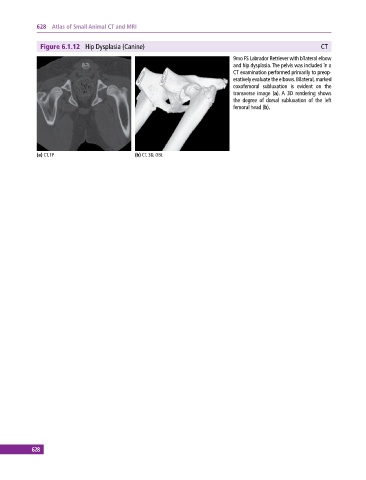

Figure 6.1.12 Hip Dysplasia (Canine) CT

9mo FS Labrador Retriever with bilateral elbow

and hip dysplasia. The pelvis was included in a

CT examination performed primarily to preop

eratively evaluate the elbows. Bilateral, marked

coxofemoral subluxation is evident on the

transverse image (a). A 3D rendering shows

the degree of dorsal subluxation of the left

femoral head (b).

(a) CT, TP (b) CT, 3D, OBL